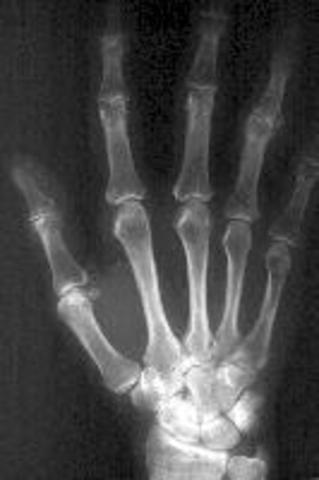

• RAYOS X

RAYOS X

De casi todos son conocidas las aplicaciones de los rayos X en el campo de la Medicina para realizar radiografías, angiografías (estudio de los vasos sanguíneos) o las llamadas tomografías computarizadas. Y el uso de los rayos X se ha extendido también a la detección de fallos en metales o análisis de pinturas.